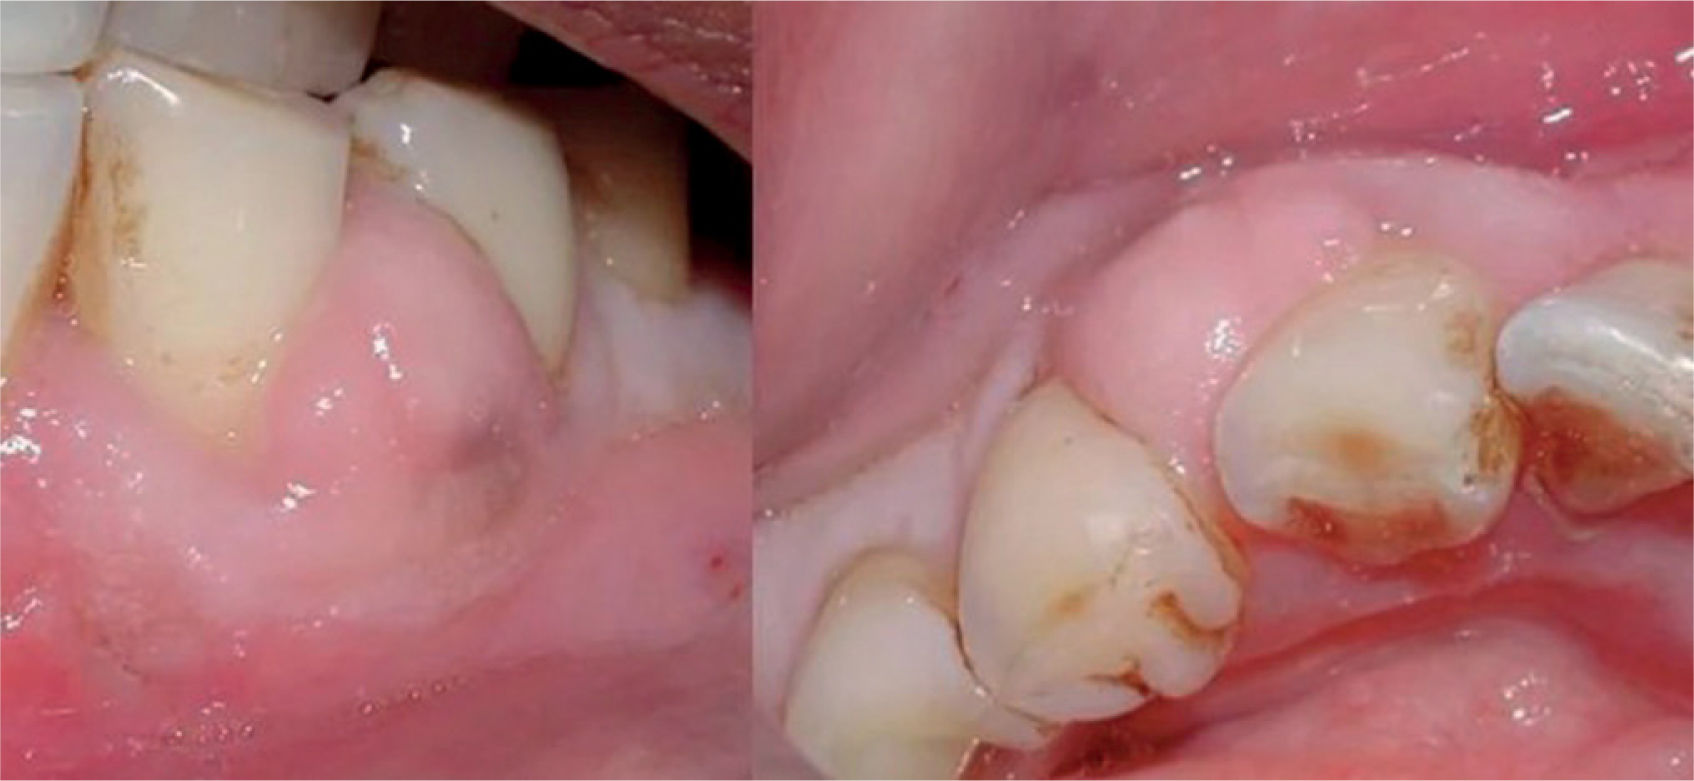

Clínica. Inicialmente es asintomática (fig. 3) hasta que alcanza tejidos dentales profundos (pulpitis).

Periodontitis o piorrea: progresión de la inflamación gingival (fig. 6) que afecta a las estructuras de soporte del diente. Inicialmente asintomática, su avance supone la destrucción de las estructuras que fijan el diente, pérdida de hueso maxilar y, finalmente, la caída de la pieza dental. Afecta al 30% de los adultos y es más frecuente en varones5.

El sarro dental (también conocido como cálculo o tártaro dental) es consecuencia de la acumulación y endurecimiento de la placa bacteriana entre los dientes y la línea de las encías (fig. 7). El sarro está formado por bacterias, restos de saliva, restos de alimentos y células muertas que no se eliminan correctamente con la higiene dental. Una vez se ha formado, no puede ser eliminado con la higiene oral habitual y precisa de una limpieza exhaustiva por parte del odontólogo o higienista dental.

Es un factor de riesgo para la aparición de caries, enfermedad periodontal, gingivitis, halitosis y en estados avanzados, de pérdida de piezas dentales6.